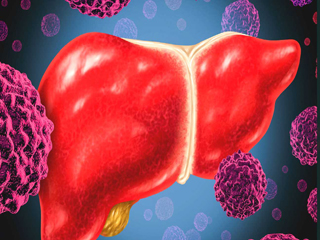

हेपेटाइटिस बी और सी वायरस और कुछ प्रकार के एचपीवी लिवर और सर्वाइकल (गर्भाशय ग्रीवा) कैंसर के लिए खतरा बढ़ाते हैं। एचआईवी के साथ संक्रमण से सर्वाइकल कैंसर जैसे कैंसर का खतरा काफी बढ़ जाता है।

• लिवर कैंसर (782 000 मौतें)